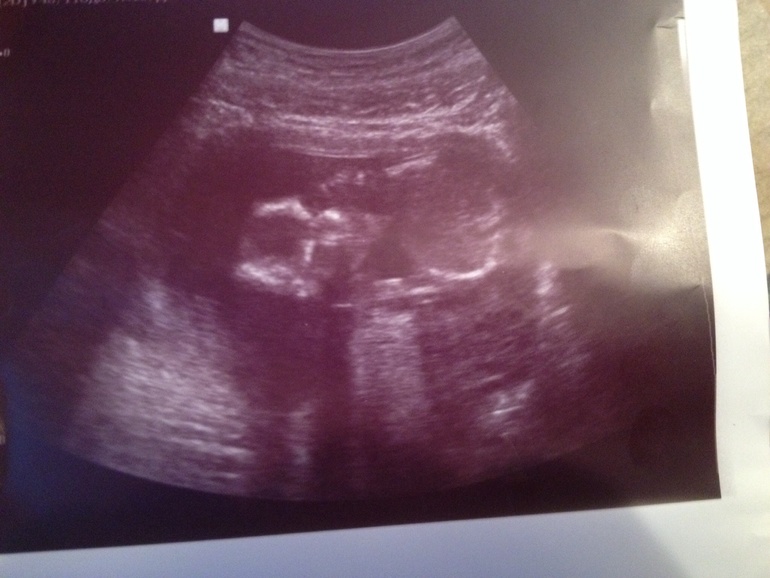

Алина 11 лет Доченька!!! Растем здоровые и длинные) Врач говорит, что родиться будущая модель) Мы очень ждем тебя, Маруся! Посмотрите еще 20 записей на эту тему Отменить Ответить Узи! Первые шевеления! Чаты Беременных Выберите чат: Январята-2026 Февралята-2026 Мартята-2026 Апрелята-2026 Майчата-2026 Июнята-2026 Июлята-2026 Августята-2026